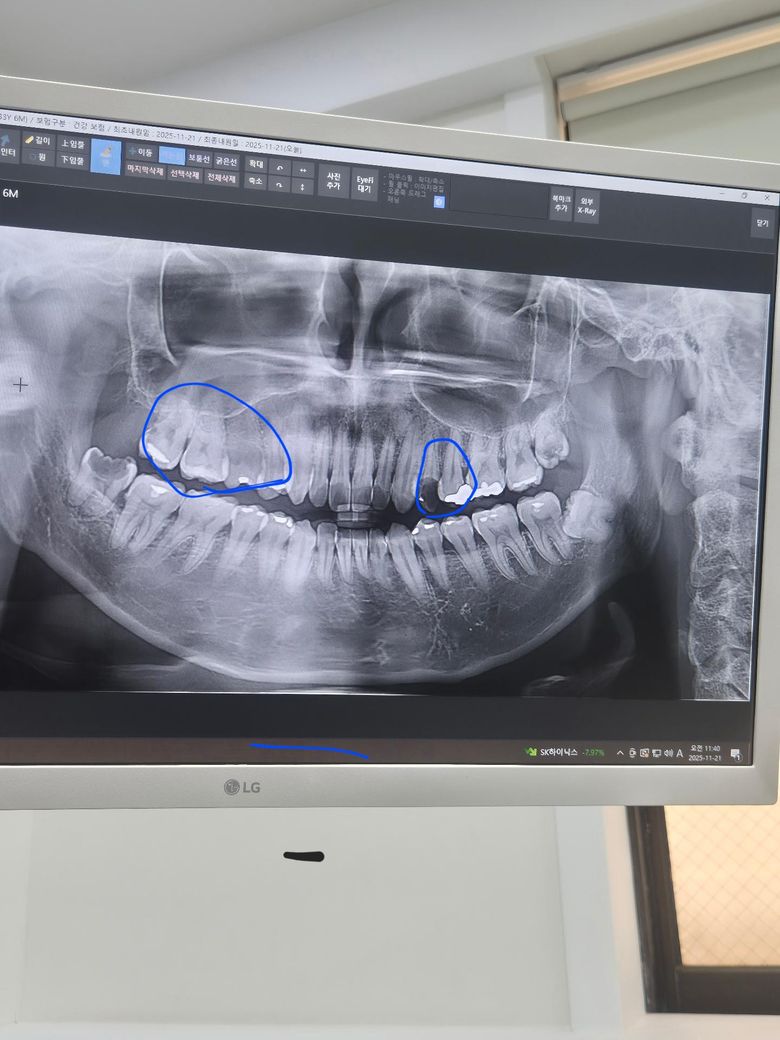

제 이빨 엑스레이만 봤을때 신경치료가 필요할까요?

파란색 동그라미 부분에 충치가 있어서 씹거나 차가운 것이 닿으면 많이 시립니다

작은 동그라미에 검은색 부분은 이가 살짝 깨져있어요

사진상으로 왼쪽에 있는 가장뒤 치아는 뒤쪽으로 충치가 진행되서 신경치료를 해야될것같고, 오른쪽 치아는 발치를 해야될것같습니다.

1. 파노라마 사진상 보이기로는 오른쪽 위 치아들 중 신경치료가 당장 필요한 정도로 깊은 충치가 있진 않습니다

2. 다만 증상으로 씹을때 아프다면 크랙이 의심되므로 신경치료가 필요할 수 있습니다